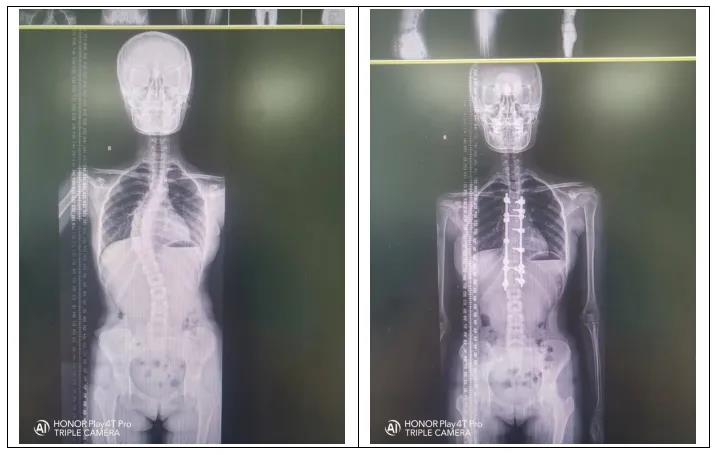

脊柱侧弯:又称脊柱侧凸,它是一种脊柱的三维畸形,包括矢状位、冠状位和轴位的序列异常。如果正位全脊柱X线片显示cobb角大于10°的侧方弯曲,即可诊断。

当Cobb角大于40°,可选择手术治疗

4、手术治疗

青少年特发性脊柱侧弯的手术指征:侧弯角度 >40° ,支具治疗无效,侧弯进展速度>5°/年和外观畸形明显者。手术治疗是通过钛合金或不锈钢螺钉和棒等内固定技术将弯曲的脊柱慢慢拉直固定,然后将移植骨覆盖于脊柱后方使弯曲的脊柱长在一 起,从而达到预防脊柱弯曲加重,改善心肺及消化功能的目的。